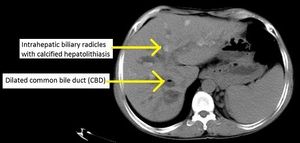

과거에는 주로 내시경 역행 쓸개이자조영(ERCP)을 통해 담관을 촬영했다. ERCP에서는 간 안팎의 담관이 염주 모양(좁아짐과 넓어짐이 반복되는 형태)으로 보이는 특징적인 소견이 나타난다. 그러나 ERCP는 침습적인 검사이다. 현재는 비침습적이면서도 정확도가 높은 자기 공명 쓸개이자조영(MRCP)이 진단적 담관 조영술에 선호되는 방법이다. MRCP는 자기 공명 영상(MRI) 기술을 이용하며, 공간 해상도가 높아 미세한 담관 구조까지 시각화할 수 있다.[21] 복부 초음파 검사나 컴퓨터 단층 촬영(CT)도 보조적으로 사용될 수 있다.